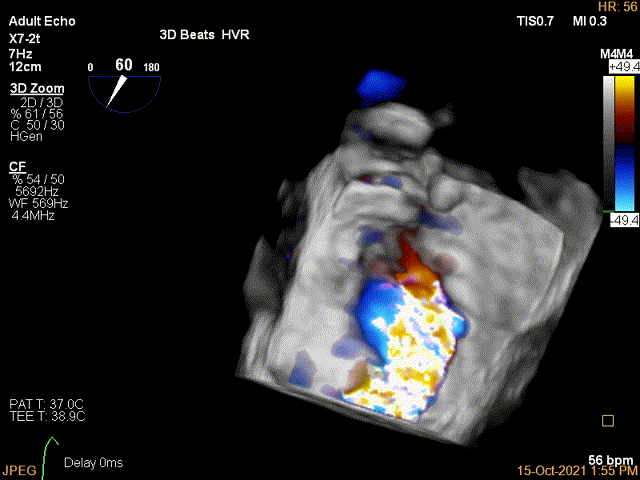

3D-color MV view:极大量返流,1、2区均有受累

3D-color证实残余分流主要位于内侧2区

Color第二个夹子内侧残余小束分流,宽2.3mm